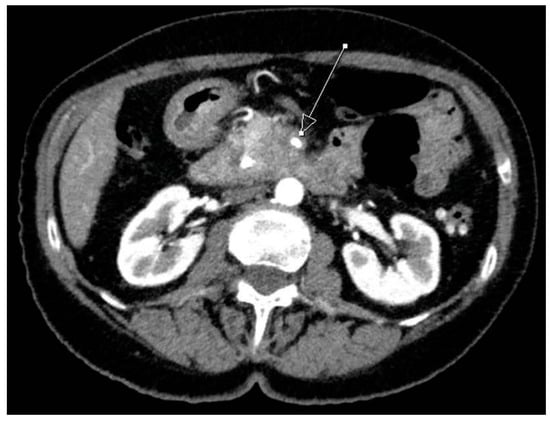

2. Definition of Resectability